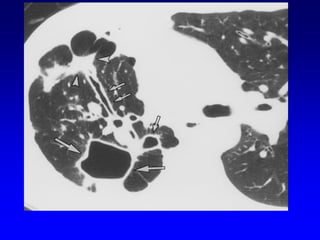

Upper lobe Bulla

Lower lobe Bulla

A: Xray shows bilateral bulla.

B: CT shows bilateral bulla.

C: CT after bullectomy.